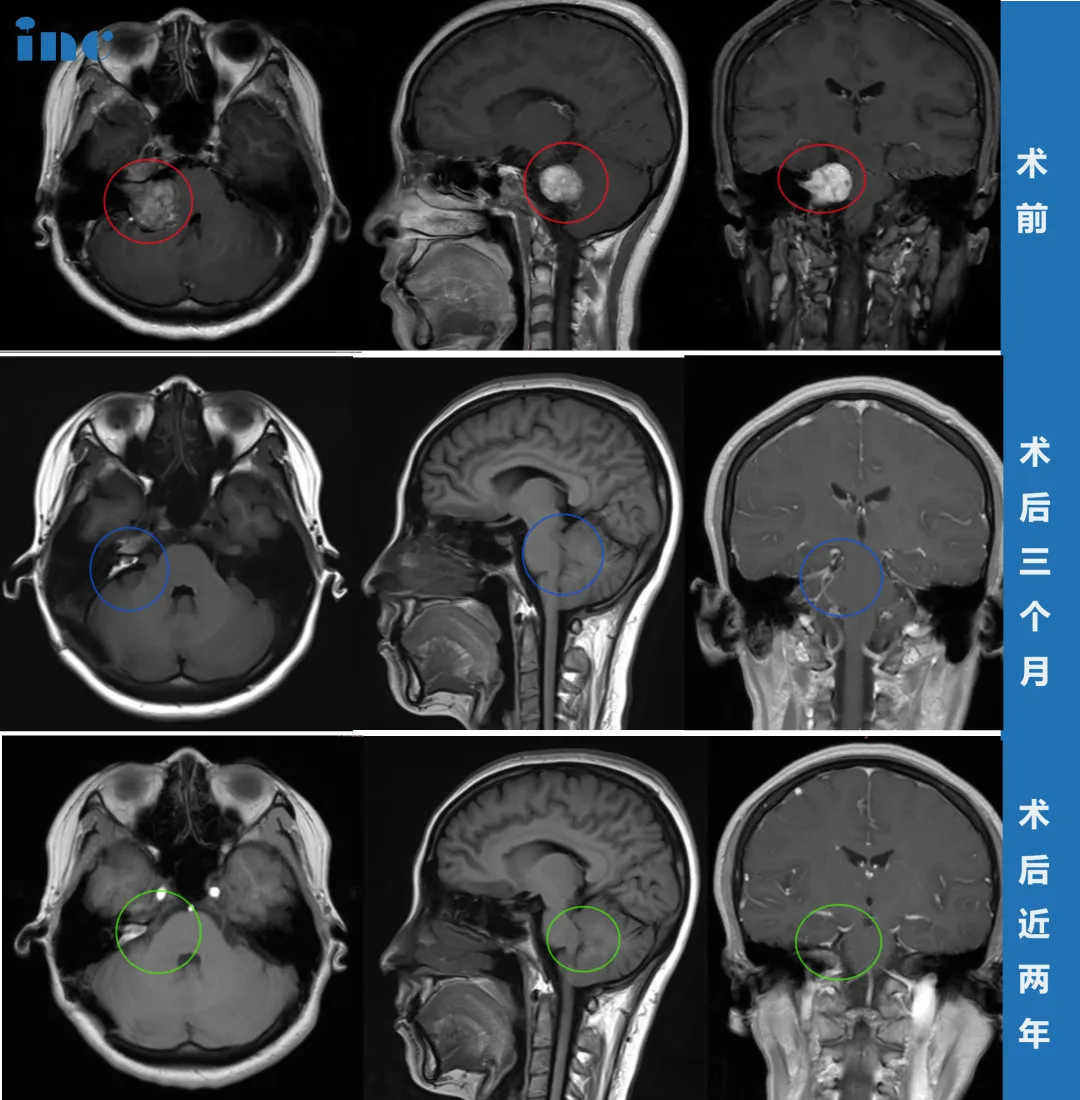

术前:右侧CPA区前庭神经鞘瘤,病灶大小约为3.5cm,累及右侧内听道内,增强扫描显示明显强化,桥脑及右侧桥臂受压,四脑室变形。术后:在术中神经电生理监测下,精准全切肿瘤,术中无新发神经功能障碍;术后3个月面神经恢复良好;术后近2年没有复发。